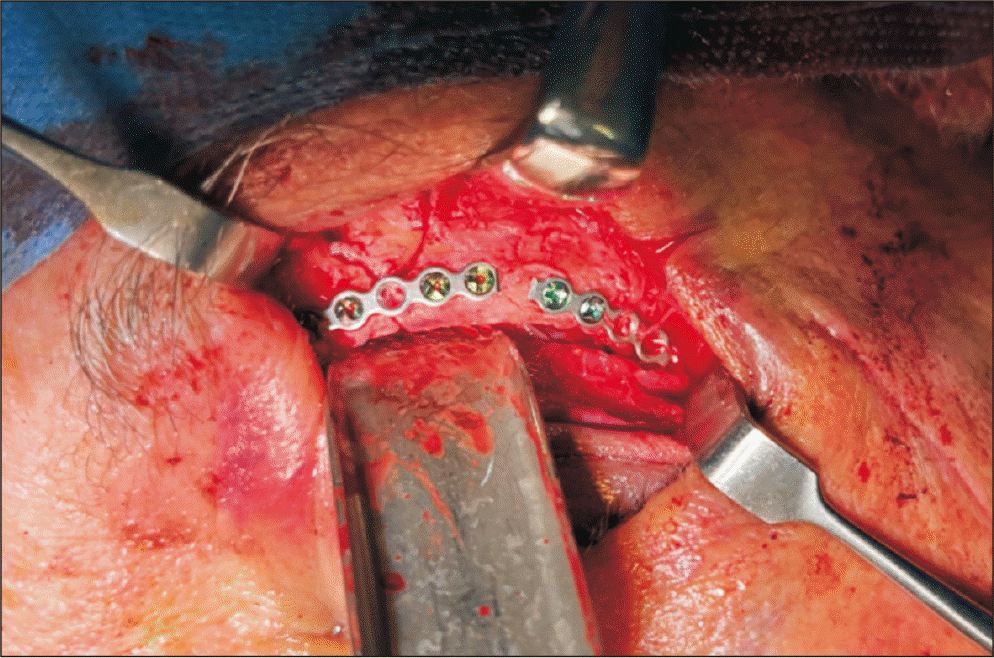

For the surgical procedure, 1 cc of 2% lidocaine with 1:100,000 epinephrine was infiltrated under the eyelid skin and orbicularis oculi muscle, and an additional 0.5 cc was injected into the lateral canthal region. The cornea was protected with a plastic shield following the application of ophthalmic ointment. A skin incision was made along the supratarsal crease, extending 5 mm toward the lateral canthus. Dissection was performed through the orbicularis oculi muscle to expose the fracture site, which was then reduced and stabilized with osteosynthesis.(Fig. 3) Wound closure was carried out in three layers—periosteum, muscle, and skin—with meticulous alignment of the lateral canthal structures. The procedure was completed without intraoperative complications.

Fig. 3

Intraoperative reduction and osteosynthesis of fronto-orbito-zygomatic fracture using an upper eyelid approach with lateral canthotomy of the left orbit.